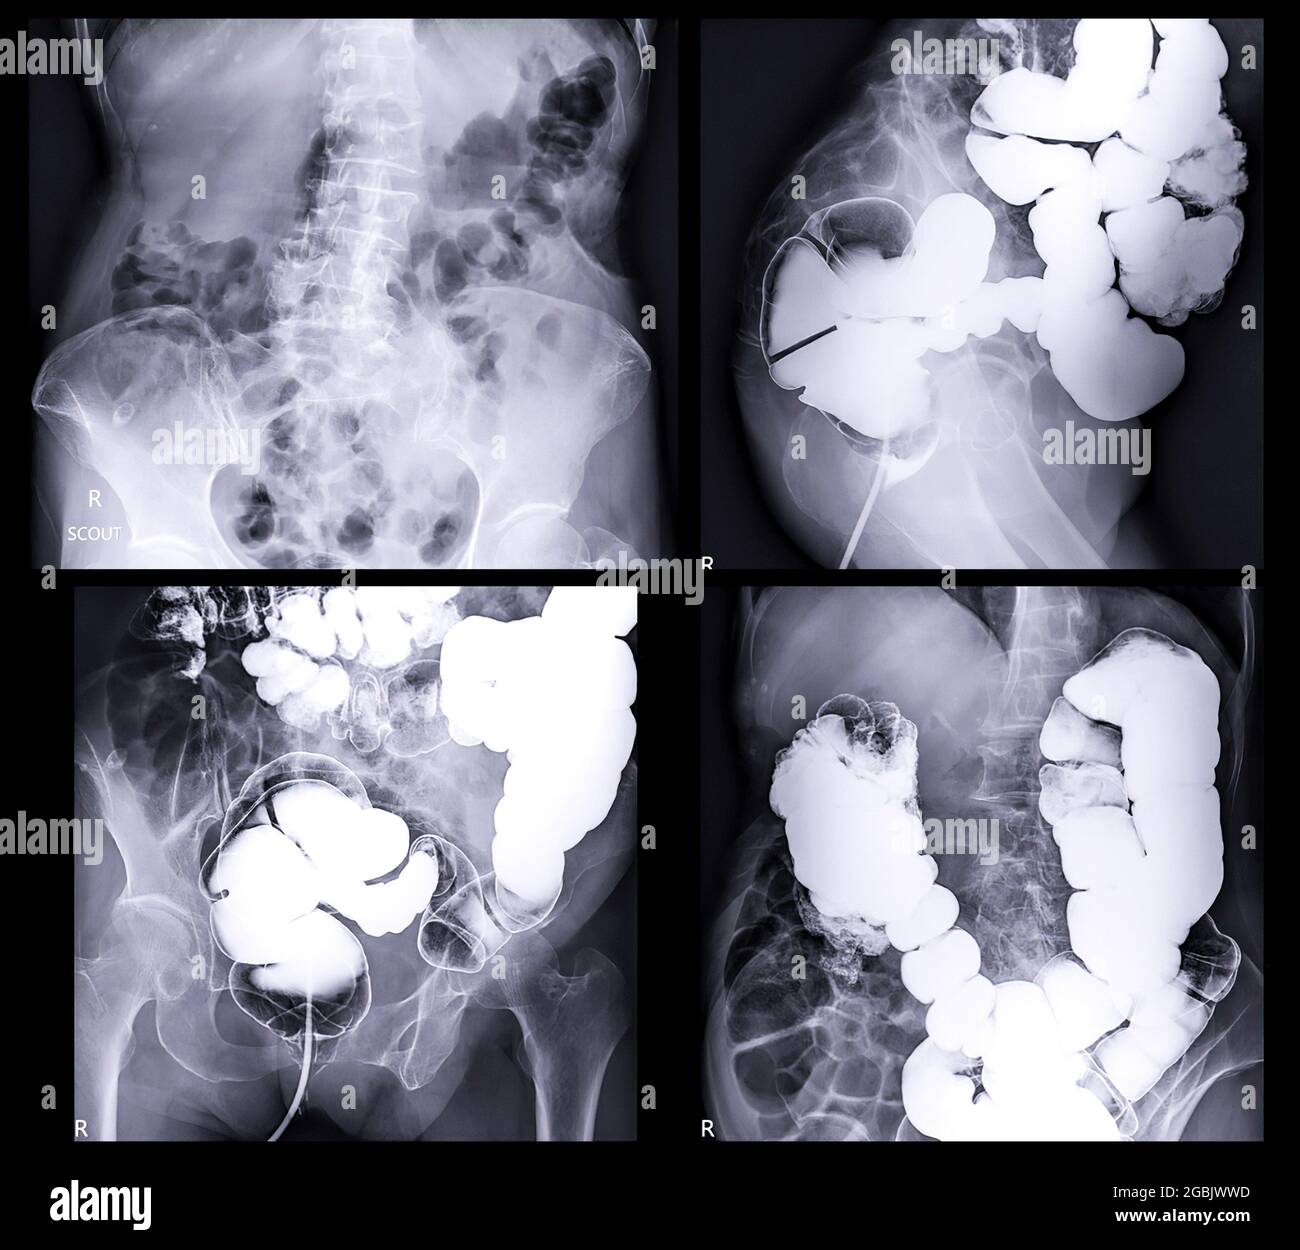

From www.alamy.com

barium enema demonstrated cecum and colon for diagnosis Colorectal Instant Enema Radiology The instant enema works well in ulcerative colitis as the diseased bowel is in continuity from its distal to its proximal extent, and free of formed. Technique, indications, results and limitations of a conventional imaging methodology in the mdct. The instant, or unprepared, double contrast barium enema has been used routinely at st mark's hospital in the investigation of active.. Instant Enema Radiology.